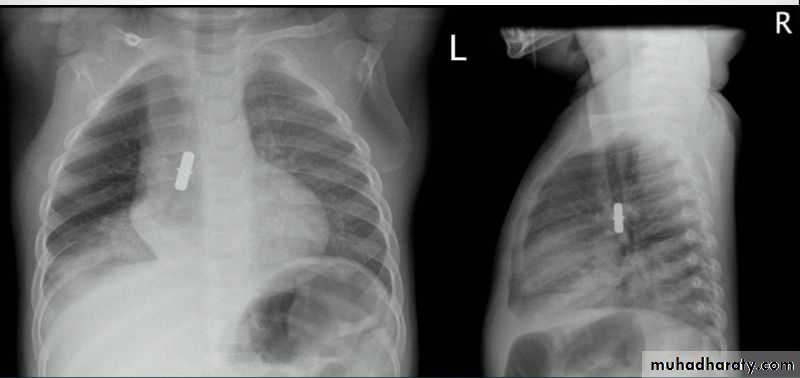

Fall from the 2nd floor

History; too shy to take of his shirt in the pool!